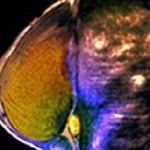

After Mammography, Abbreviated MRI Protocol Can Exclude Malignancy

An abbreviated magnetic resonance imaging (MRI) protocol can exclude malignancy in women with suspicious X-ray mammography screening, according to a study published in Radiology. Sebastian Bickelhaupt, M.D., from the German Cancer Research Center in Heidelberg, and colleagues conducted a prospective study involving 50 women with suspicious screening X-ray mammograms. The … [Read more...] about After Mammography, Abbreviated MRI Protocol Can Exclude Malignancy